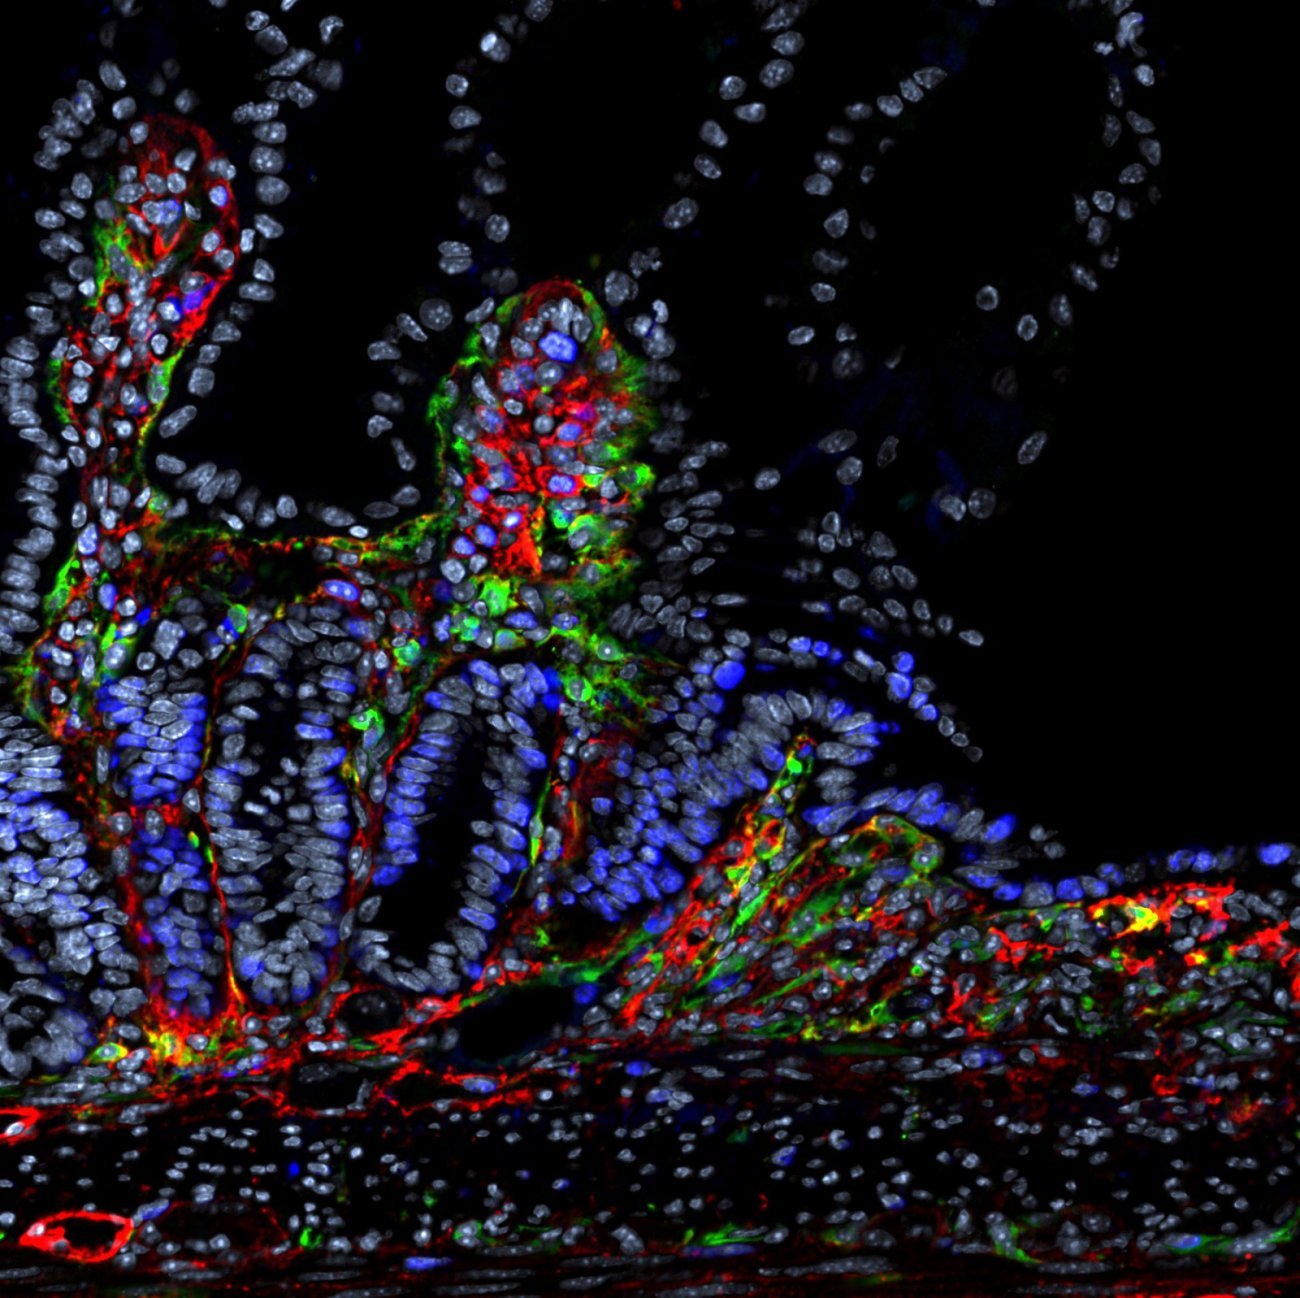

L’équipe de Molly Ingersoll s’attaque précisément à cette énigme en étudiant les sites muqueux sous-explorés comme la vessie. Leur hypothèse repose sur l’influence des hormones stéroïdiennes (oestrogènes, progestérone, androgènes cortisol), qui agissent comme des modulateurs puissants du système immunitaire. Pour y répondre, l’équipe a collaboré avec le consortium “Milieu Intérieur” et a analysé 17 hormones différentes dans le sang des volontaires de la cohorte, dont environ 500 sont revenus pour fournir à nouveau des échantillons dix ans plus tard.

Notre système immunitaire n’est pas statique : il évolue tout au long de la vie, façonné par des facteurs comme l’âge, le sexe ou l’histoire vaccinale. Grâce à des technologies de pointe comme le single-cell sequencing, ces variations peuvent être analysées, révélant les mécanismes du déclin immunitaire lié à l’âge.

Le séquençage de cellule unique (single-cell sequencing) est une technologie de pointe analysant l’ARN cellule par cellule, révélant leur diversité et leur fonctionnement individuel. Grâce à des systèmes microfluidiques, elle identifie des sous-populations cellulaires – comme des cellules tumorales résistantes aux traitements – ou des sous-populations rares apparaissant avec l’âge indétectables par les méthodes classiques. En oncologie, elle permet de distinguer les cellules saines des cellules malignes et d’affiner les cibles thérapeutiques. Cette approche révolutionne les diagnostics, les traitements personnalisés et la compréhension des maladies.

En exposant in vitro les cellules sanguines de 380 individus de la cohorte “Milieu Intérieur” à des pathogènes comme le SARS-CoV-2 ou le virus de la grippe, il a été démontré que les personnes âgées présentent une réponse immunitaire affaiblie, notamment en raison d’une production réduite d’interféron alpha, une protéine cruciale pour bloquer la réplication virale. « Parallèlement, l’analyse de l’ensemble des gènes montre que les lymphocytes T CD4 sont le type cellulaire le plus impacté par l’âge », complète le chercheur.

Leurs travaux confirment également que les femmes bénéficient d’une réponse immunitaire plus robuste que les hommes, un paradoxe connu sous le nom de mortality-morbidity paradox : bien qu’elles vivent en moyenne plus longtemps, elles sont aussi plus sujettes aux maladies auto-immunes. « Chez les femmes, les cellules immunitaires innées, comme les cellules myéloïdes, réagissent plus vigoureusement aux virus, avec une expression accrue de gènes proinflammatoires», précise le chercheur. Cette supériorité s’explique en partie par leurs deux chromosomes X : certains gènes échappent à l’inactivation du second chromosome X, leur offrant un avantage immunologique.